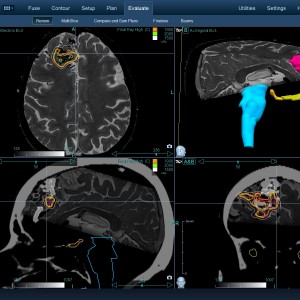

Στις παρακάτω φωτογραφίες θα δείτε παραδείγματα πλάνων θεραπείας καρκινικών όγκων με CyberKnife. Παρατηρήστε πόσο κοντά στους υγιείς ιστούς βρίσκονται οι καρκινικοί όγκοι που χρειάζεται να ακτινοβοληθούν. Μόνο με το CyberKnife και το προσωπικό πλάνο θεραπείας, μπορούν να ακτινοβοληθούν οι όγκοι χωρίς να πληγούν οι παρακείμενοι υγιείς ιστοί.

Μόνο με το CyberKnife και την κατάλληλη σχεδίαση της θεραπείας από έμπειρο νευροχειρουργό, μπορεί να ακτινοβοληθούν οι όγκοι χωρίς να επηρεαστούν από την ακτινοβολία οι υγιείς ιστοί. Αυτό εξασφαλίζει τη μέγιστη δυνατή απόδοση της ακτινοχειρουργικής θεραπείας των όγκων.

Με κόκκινο χρώμα περιγράφεται η περιοχή του όγκου.

Με μπλε, κίτρινο και πράσινο χρώμα περιγράφονται οι υγιείς ιστοί που δεν πρέπει να ακτινοβοληθούν.

Παρατηρήστε πόσο κοντά βρίσκεται ο όγκος με τους υγιείς ιστούς.